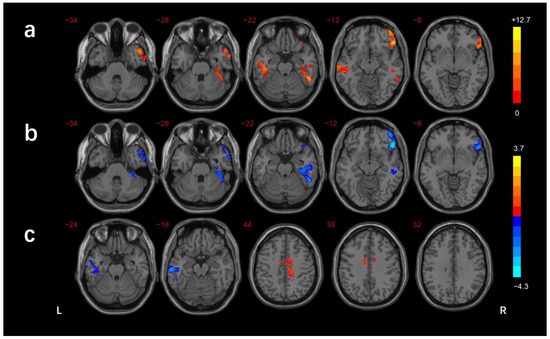

| Brain Regions | BA | Voxels (mm3) | Peak MNI Coordinates | f/t-Value | ||

|---|---|---|---|---|---|---|

| X | Y | Z | ||||

| ANOVA | ||||||

| R_MTG/ITG | 21/38 | 194 | 51 | 9 | −39 | 10.514 |

| R_MTG/ITG/FG/cerebellar lobule VI | 37/20 | 187 | 54 | −48 | −18 | 11.278 |

| L_ITG | 21 | 155 | −60 | −21 | −15 | 10.434 |

| R_IFG | 47 | 206 | 51 | 33 | −15 | 12.651 |

| DMCN vs. HC | ||||||

| L_MTG/ITG | 21 | 188 | −66 | −24 | −15 | −3.975 |

| B_MCC/R_precuneus | 24 | 188 | 15 | −24 | 42 | 3.665 |

| DMCI vs. HC | ||||||

| R_MTG/ITG | 21/38 | 185 | 51 | 12 | −45 | −4.018 |

| R_MTG/FG/cerebellar lobule VI | 37/20 | 299 | 39 | −24 | −18 | −3.908 |

| R_IFG | 47 | 229 | 48 | 30 | −12 | −4.243 |